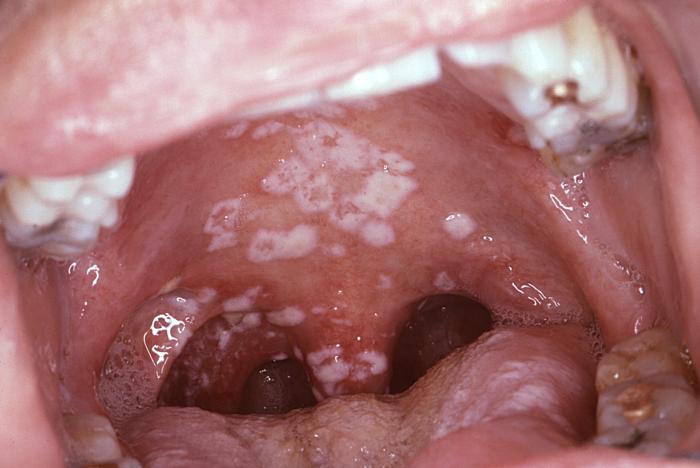

Кандидоз полости рта фото

Обычно симптомы кандидоза полости рта у детей проявляются на внутренней стороне щек, но поражению могут быть подвержены и язык, небо, глотка, миндалины. В начале заболевания диагностика довольно сложна: характерный налет отсутствует, слегка краснеет слизистая оболочка ротовой полости. Спустя какое-то время образуется налет, похожий на манную крупу, постепенно превращающийся на вид в молочную пленку или творожистую массу. Белый налет легко снимается, после чего обнаруживаются ярко красные воспаленные участки, нередко с капельками крови. Даже еле заметные язвочки на языке могут свидетельствовать о заражении.

Проявляющийся белый творожистый налет представляет собой псевдомицелий, состоящий из кератина, фибрина, клеток эпителия, остатков пищи и бактерий. Налет начинается с вида белых крупинок, затем превращается в «молочные» пленки и бляшки, постепенно разрастающиеся и сливающиеся.

Поражению подвергаются не только внутренняя поверхность щек, но и язык, десна, небо, миндалины. При поражении губ, они также покрываются белыми хлопьями и чешуйками.

При легкой форме заболевания на слизистой рта появляется сыпь красного цвета, которая сверху покрывается налетом белого цвета. На следующей стадии у ребенка наблюдается отечность тканей и образование локализованных белых пятен с налетом творожной консистенции. Постепенно эти пятна сливаются в большую площадь поражения.